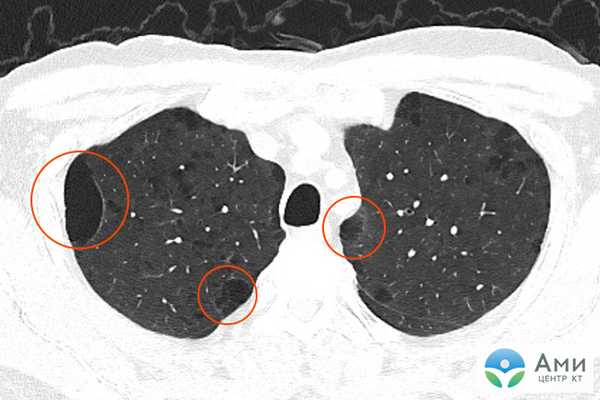

Диагностика буллезной эмфиземы легких основывается на клинических, функциональных и рентгенологических данных. Курация больного осуществляется пульмонологом, а при развитии осложнений - торакальным хирургом. Рентгенография легких не всегда эффективна в выявлении буллезной эмфиземы легких. В то же время, возможности лучевой диагностики существенно расширяет внедрение в практику КТ высокого разрешения. На томограммах буллы определяются как тонкостенные полости с четкими и ровными контурами. При сомнительном диагнозе удостовериться в наличии булл позволяет диагностическая торакоскопия.

Буллы в легких на КТ

Буллы в легких на КТ визуализируются как отчетливые, сравнительно более затемненные пузырькообразные участки легочной ткани, напоминающие дыры или крупные поры губки. Чем более плотная ткань, тем более она светлая на КТ-сканах — поэтому, например, кости белые, а воздушная легочная ткань сравнительно однородного графитно-серого цвета.

На КТ легких врач-рентгенолог может точно определить диаметр булл, их количество, выяснить, есть ли признаки эмфиземы, бронхоэктазы либо иные диффузные легочные заболевания.